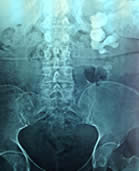

Κάποτε, λόγω του μεγάλου μεγέθους του λίθου χρειάζονται περισσότεροι τέτοιοι δρόμοι όπως στις φωτογραφίες.

Αυτή η δυνατότητα είναι πολύ σημαντική σε περιπτώσεις με λίθους σε κάθε σημείο του νεφρού όπως στην φωτογραφία.